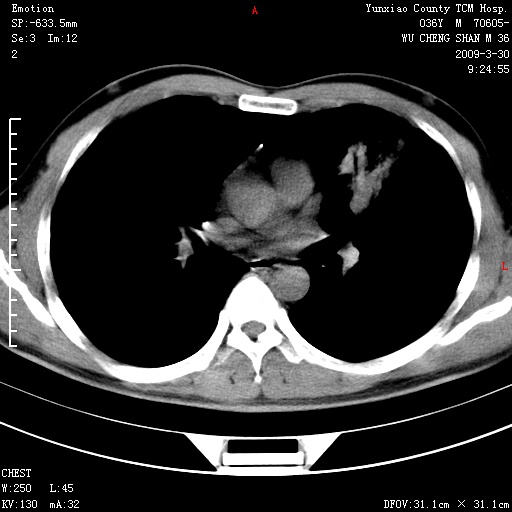

本院家属,胸痛,无咳嗽咳痰发烧病史,治疗一个月后病灶无明显改变,支气管镜示左肺慢性炎症,未见癌细胞,

胸痛,无咳嗽咳痰发烧病史,治疗一个月后病灶无明显改变,支气管镜示左肺慢性炎症,未见癌细胞,左肺下叶前段片状影,边缘不清,内见空支气管征,纵隔未见淋巴结肿大,周围无卫星灶,应考虑为炎性病变。

胸痛,无咳嗽咳痰发烧病史,治疗一个月后病灶无明显改变,支气管镜示左肺慢性炎症,未见癌细胞,左肺舌叶片状影,边缘不清,内见空支气管征,周围无卫星灶,应考虑为炎性病变。

左肺舌叶片状影,边缘不清,内见空支气管征,炎性病变